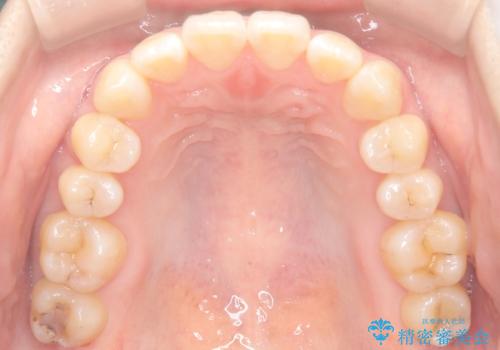

下顎前歯の叢生が整い、右下5番部には機能的かつ審美的なインプラント補綴が完了しました。

咬合全体のバランスも改善し、長期的な安定性が期待される状態となりました。

患者様にも「長年気になっていた前歯のがたつきも一緒に治せてよかった」と喜んでいただけました。